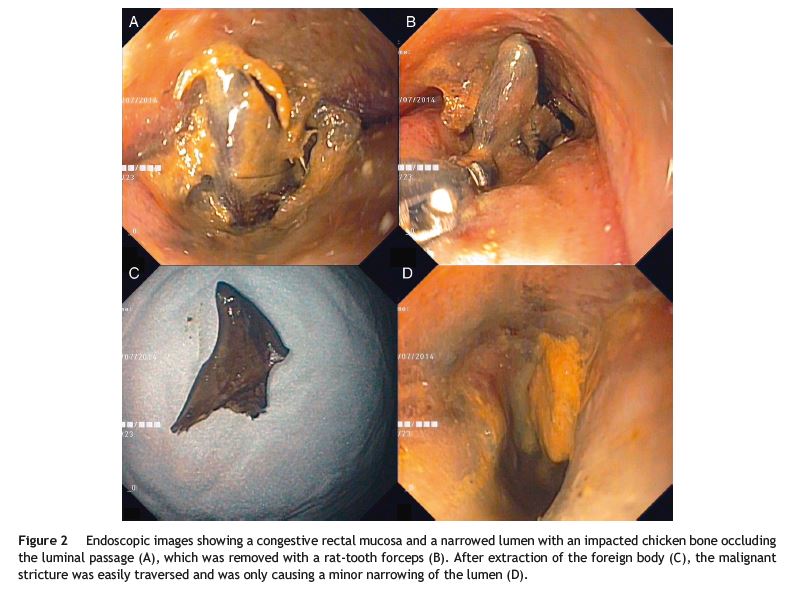

A 51-year-old man presented with a 1-day history of intense abdominal pain, vomiting, constipation and inability to pass gas. His past medical condition comprised an advanced gastric SRC (T3N2M0), diagnosed when the patient was 47 years old. He was submitted to distal gastrectomy and adjuvant chemotherapy and three years later, palliative chemoradiotherapy for non-obstructive rectal and prostate metastasis. Physical examination revealed no signs of peritoneal irritation. Laboratory tests showed an acute kidney injury. An abdominal X-ray demonstrated marked colonic distension and computed tomography (CT) revealed a malignant rectal stenosis with proximal colonic dilation (Fig. 1A-C). Considering his medical condition, the patient was referred for palliative stenting and underwent a sigmoidoscopy. The sigmoidoscopy depicted a malignant stricture with an impacted chicken bone leading to edema and complete obstruction (Fig. 2A). After removal of the foreign body with a rat-tooth forceps (Fig. 2B and C), the colonoscope was easily passed beyond the stricture (Fig. 2D). Due to reestablishment of bowel movements, stenting was postponed. Upon CT review, a radiopaque object was found within the rectal stricture (Fig. 1C).